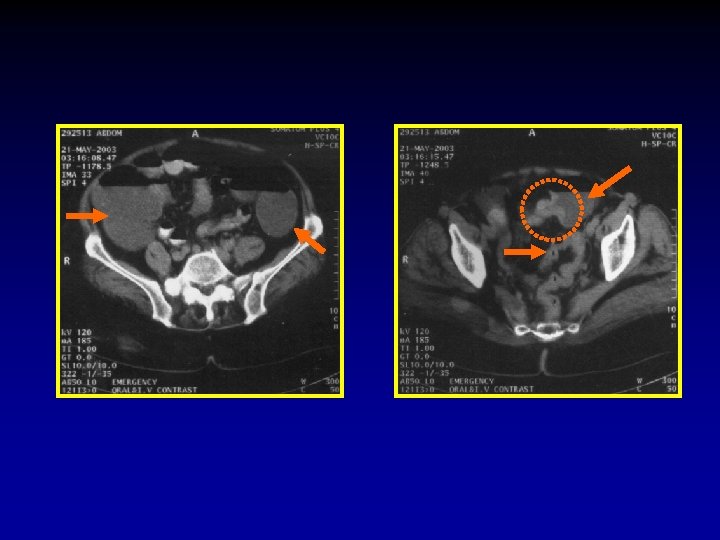

3. What is the level of obstruction? In order to detect the exact level, systematic evaluation should begin at the rectum and proceed towards the caecum. Once the colon is cleared one should attempt to identify the distal ileal loops then proceed up. A common error is to assume that loops in more caudal images are ileal loops and jejunal loops in the proximal images, in fact when the bowel loops dilate they align themselves along the axis of the mesentery thus jejunal loops may appear in the pelvis and ileal loops in the upper abdomen. In small bowel obstruction the transverse colon will not be seen because it is compressed against the anterior abdominal wall by the tensely distended small bowel loops.